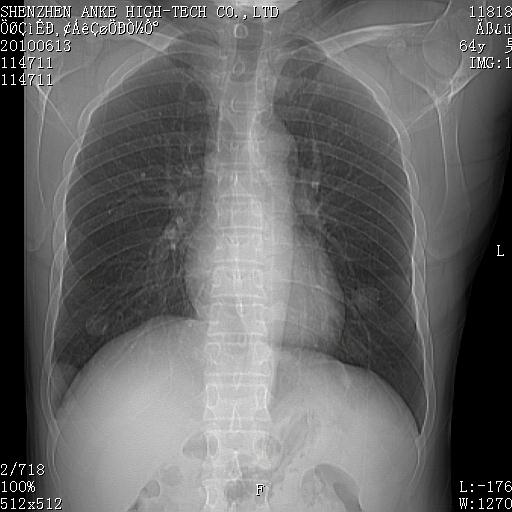

以下是引用beifangren在2010-7-26 22:05:00的发言:[br]左肾中极圆形占位,肾盏肾盂受压移位,建议增强。结合肺部结节。肝低密度灶,多为肾癌并肺部、肝转移。